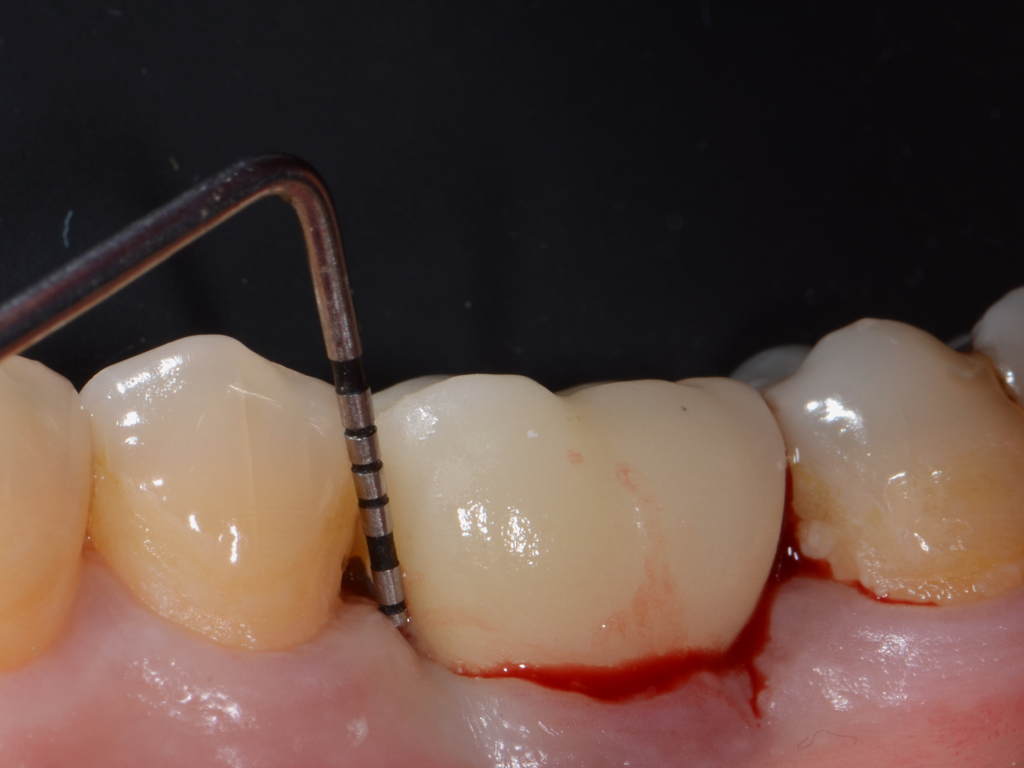

Clinical PPD is measured to the nearest millimeter by means of a graduated periodontal probe with a standardized tip diameter of approximately 0.4 mm to 0.5 mm. Several factors can influence the measurements made with periodontal probes, including: the thickness of the probe used5; the angulation and positioning of the probe depending on anatomic features, such as the contour of the tooth surface (Figure 1 through Figure 3)6; the graduation scale of the probe5; the pressure applied on the instrument during probing6; and the degree of inflammatory cell infiltration in the soft tissue and accompanying loss of collagen.7

Fig 3. Correct angulation of the probe demonstrates 6-mm probing depth.

Figure 3